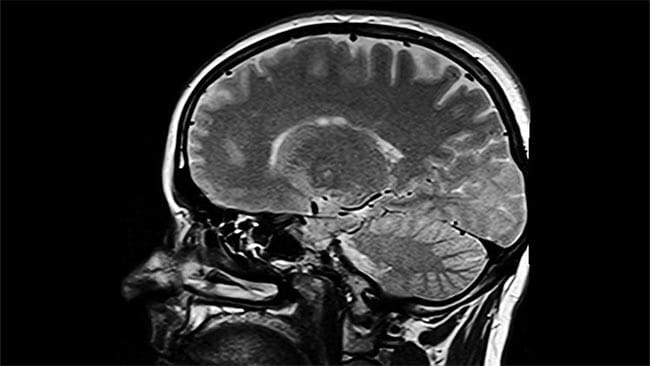

Una mujer estadounidense de 26 años se sometió a una operación que le extirparan un supuesto tumor que tenía en el cerebro. Sin embargo, la sorpresa...